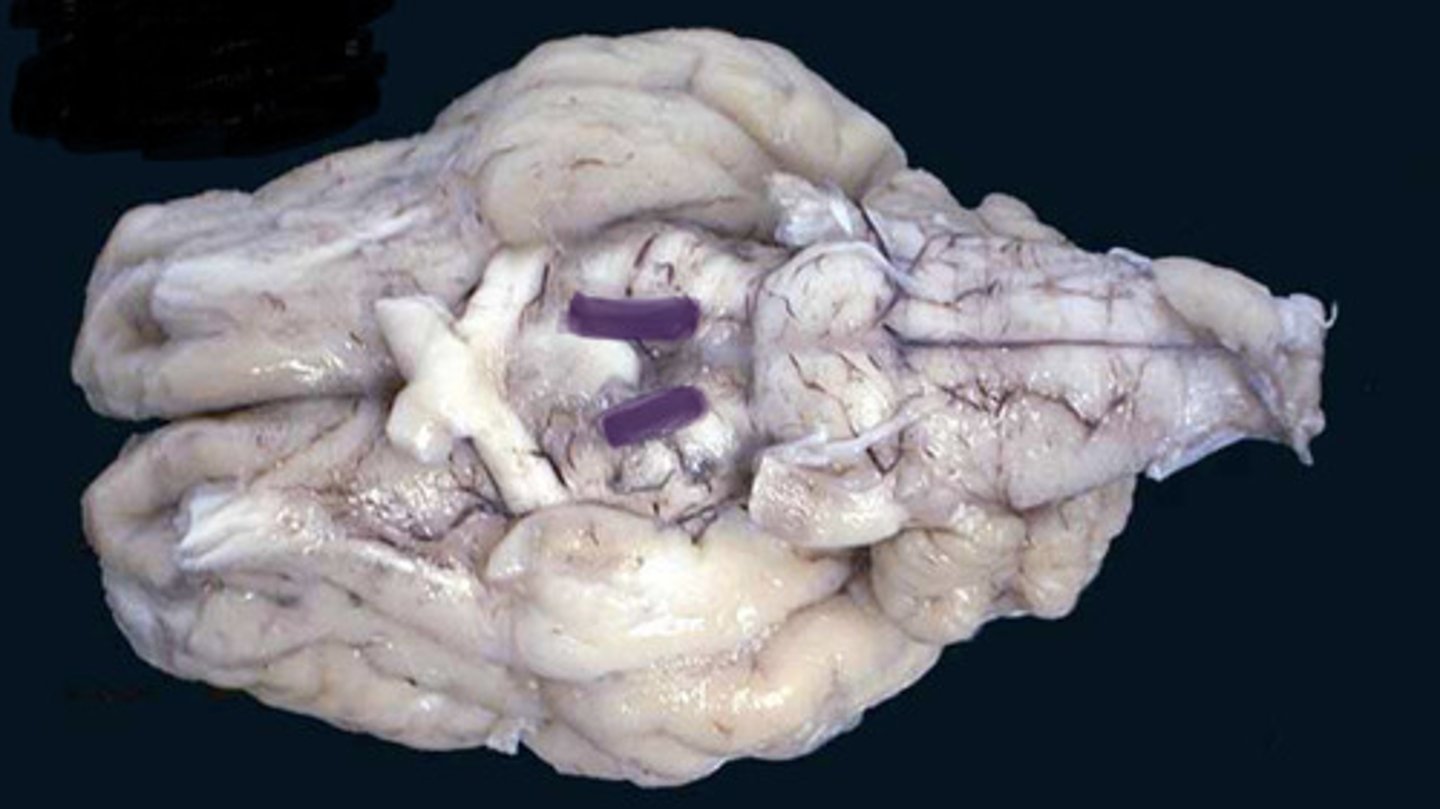

Sheep Lateral Ventricle

-produces and contains cerebrospinal fluid

Sheep Fornix

Sheep Thalamus

Sheep Corpus Callosum

Sheep Third Ventricle